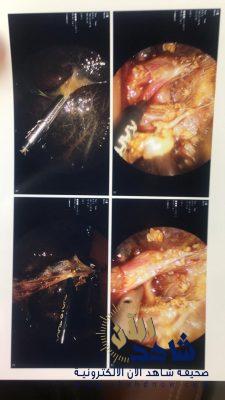

ومنها اجراء عدة عمليات لاصلاح الفتق الاربي بالمنظار الدقيق ٢ مم لاطفال حديثي ولادة وخدج وتعد من العمليات الدقيقة والمتقدمة .

كما تم إجراء عملية إصلاح فتق الحجاب الحاجز لمولود خديج تكللت بالنجاح بعدها تمكن المولود العيش بشكل طبيعي .

كما تم انهاء معاناة مريضة مقعدة تعاني من إرتجاع من المعدة والمرئ الى الرئتين وتغذيه بانبوب من الانف حيث تم عمل طي للمعدة وعمل أنبوبة تغذيه معدية بالمنظار الجراحي على أثرها مارست المريضة حياتها بشكل طبيعي .

كما تم مؤخراً إجراء أول حالة رتق قناة صفراويه بجراحة المنظار الدقيق ٢ مم و ٣ مم لطفلة حديثة الولادة